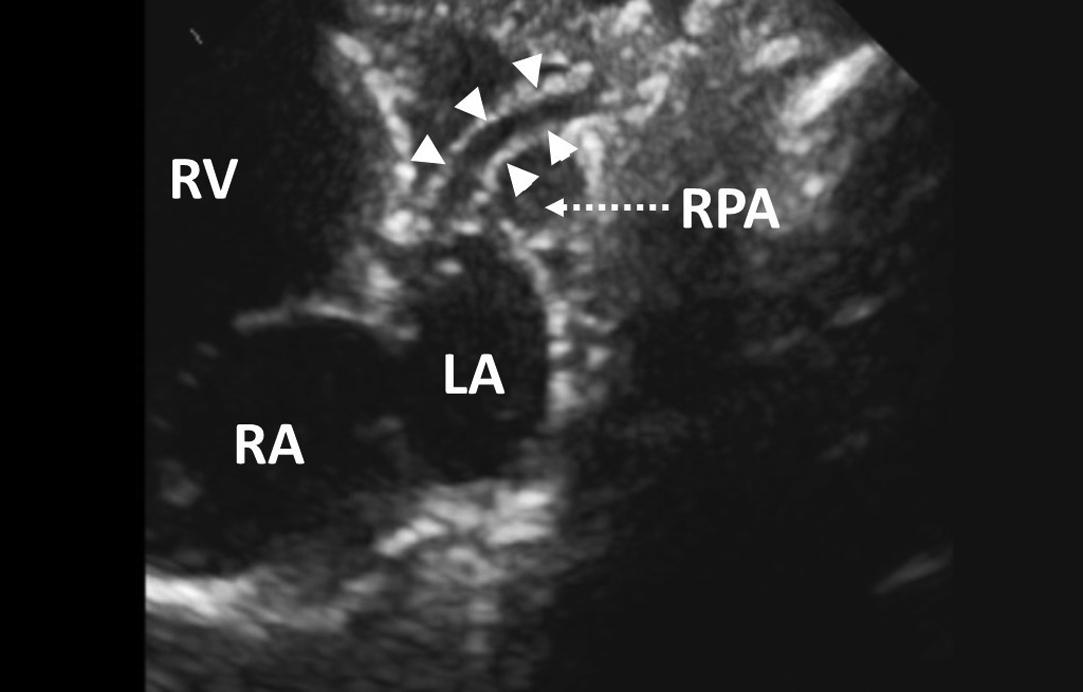

Figure 7, Modified suprasternal notch view in a neonate with hypoplastic left heart syndrome and mitral and aortic atresia. Arrowheads indicate the very hypoplastic ascending aorta, the size of which is much smaller than the diameter of the right pulmonary artery. LA , left atrium; RA , right atrium; RPA , right pulmonary artery; RV , right ventricle.